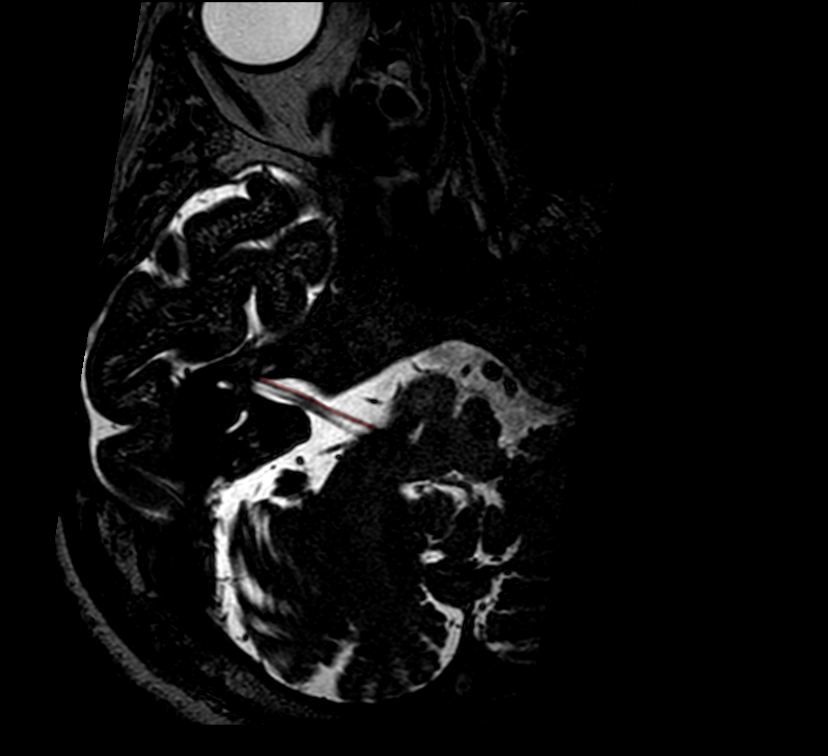

Nervus facialis im MRT

Darstellung des Nervus facialis im Verlauf vom Hirnstamm bis zum Meatus acusticus internus (Rote Markierung) in einer T2 Drive MRT Sequenz.